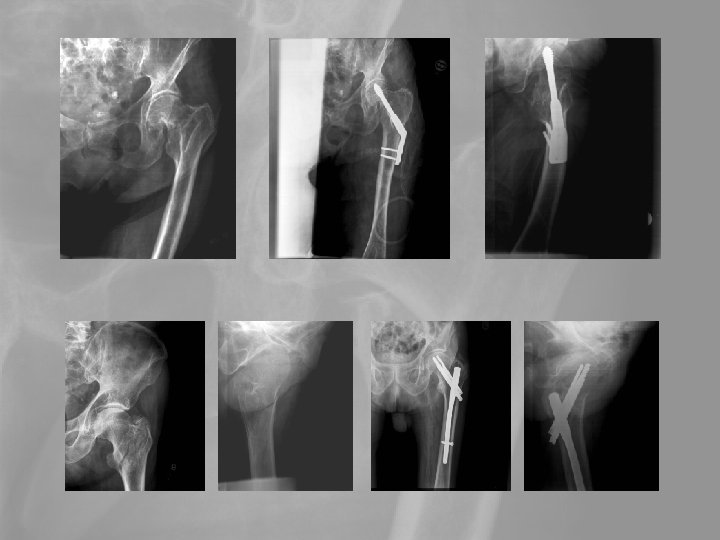

5. Medence, csípótáji törések A csípőtáji törések a leggyakrabban előforduló időskori törések. A tokon belüli törés szövődménye a fejelhalás, ami az esetek 25 -35 %-ában bekövetkezik. A tokon kívüli törések gyógyhajlama jó. A leggyakoribb szövődmény a thromboembolia, mely a az első postoperatív évben 20 -25%-os halálozással jár.

Prothesis vagy Girdlestone állapot?

Delayed revision 73 y female. Failed primary stabilisation, Delayed septic complication Pyarthros coxae, septic diaphyseal nonunion. Exarticulation?

Delayed revision Op. sec. Girdlestone+open plate-osy. Secondary wound granulation